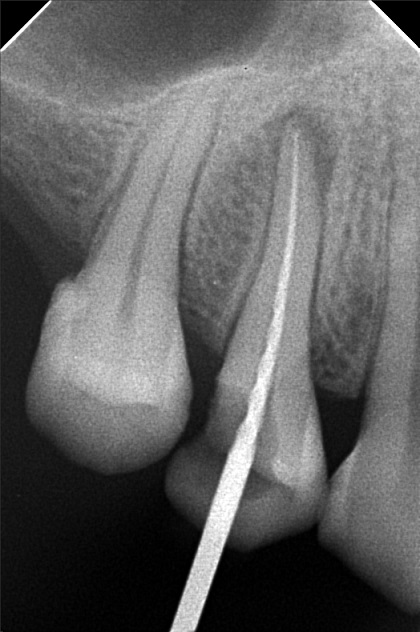

Edit Record Check our patient data records. Add patient information Patient Info Profile picture Last Name First Name Middle Name Birthdate Age Street Barangay City Country Zip Code Contact number Email Procedure 3/22/22- OP Lc 13 m/ 21 d/ 22 m/ 47 o/ b/ cervical xray 14 for rct 10/11/22 - OP (L); ACCESS #14, SCOUT #10 BL 18mm, EUGENOL. 10/14/22- 12/11/21/22- TF emax veneers 10/19/22 - 19mm, close w/ pulp devitalizer 09/02/23- op ** For change of crowns posterior Lower for Crown #15 08/13/24 OP 01/23/26 Alumina crwon #14 temporary crown OP Scanning File bangaros.jpg File 2 bongaros.jpg File 3 bongaros_02.jpg File 4 bongaros_03.jpg File 5 bongaros_04.jpg File 6 309497615_1081002115924778_349479569281481267_n.jpg File 7 bongaros_1.jpg File 8 bongaros_02_1.jpg File 9 File 10 File 11 File 12 File 13 File 14 File 15 File 16 File 17 File 18 File 19 File 20 Retain Record Retain Record Yes No Save Your Changes